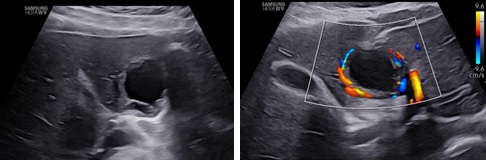

Hình ảnh siêu âm lại sau 6 tuần:

Hình 8, 9: Siêu âm lại sau 6 tuần trên thang xám và màu: khối thai viền mỏng dần với bờ không đều và những vùng hóa dịch trong thành.